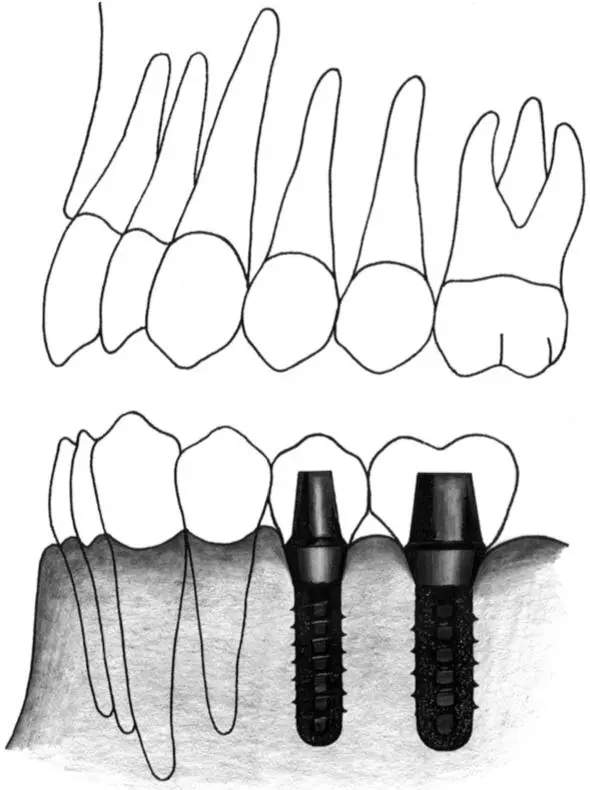

Fig 2-4 Wide neck implant.

Fig 2-4a A wide neck implant is ideal for a single-tooth gap in the first molar position.

Fig 2-4b In a posterior distal extension situation, a standard implant and a wide neck implant are ideal replacements for a missing second premolar and first molar, respectively.